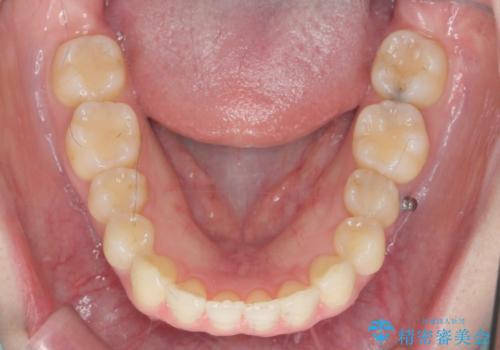

カリエール・マイクロインプラントを併用した歯の突出を改善する大きな遠心移動

- 口が閉じづらく、突出し歯が出っ歯に見えてしまうことの改善を求めて来院されました。

通常このような場合、抜歯してのワイヤー矯正治療も選択肢に入りますが、患者様の強い希望により抜歯を行わずマウスピースによる治療を選択しました。

カリエール・マイクロインプラントを用い、時間はかかりましたが大きく歯の後方移動が達成され、前歯の見た目が大きく改善されました。